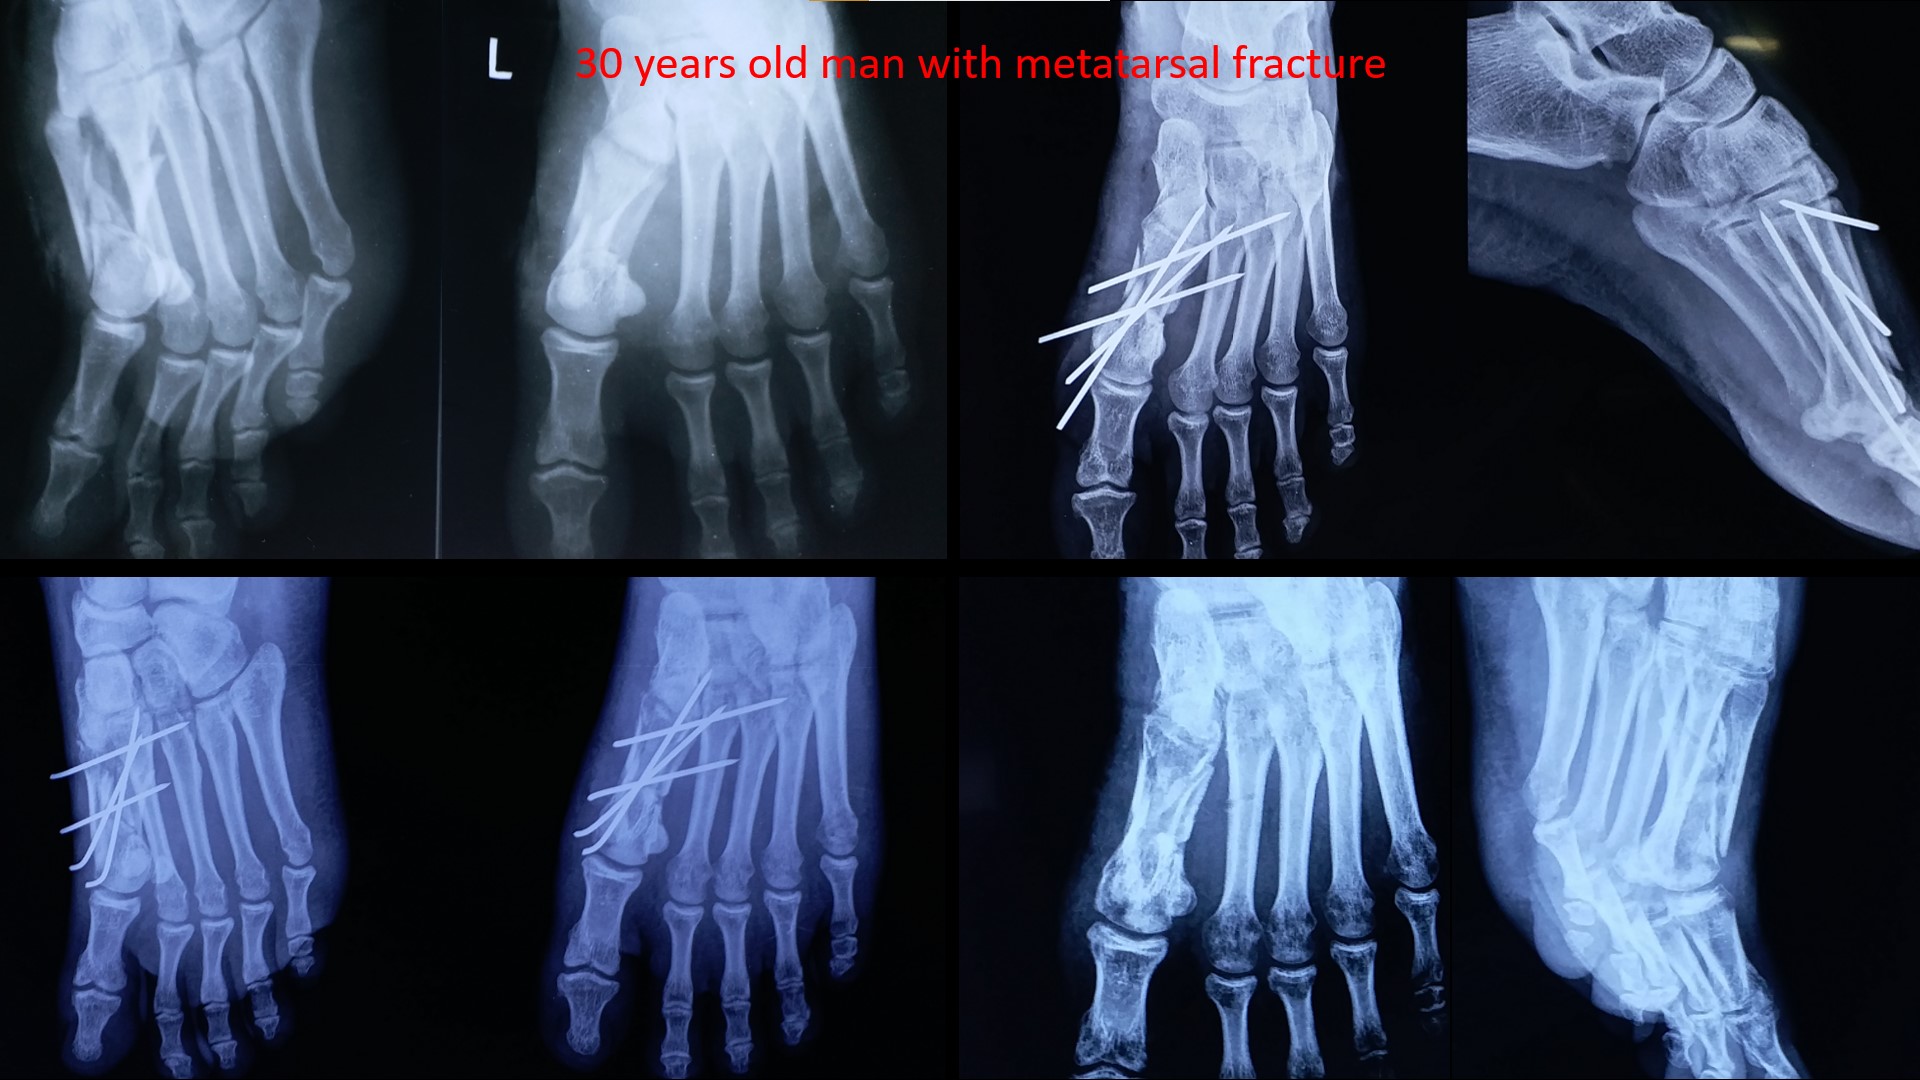

MIDTARSAL INJURY